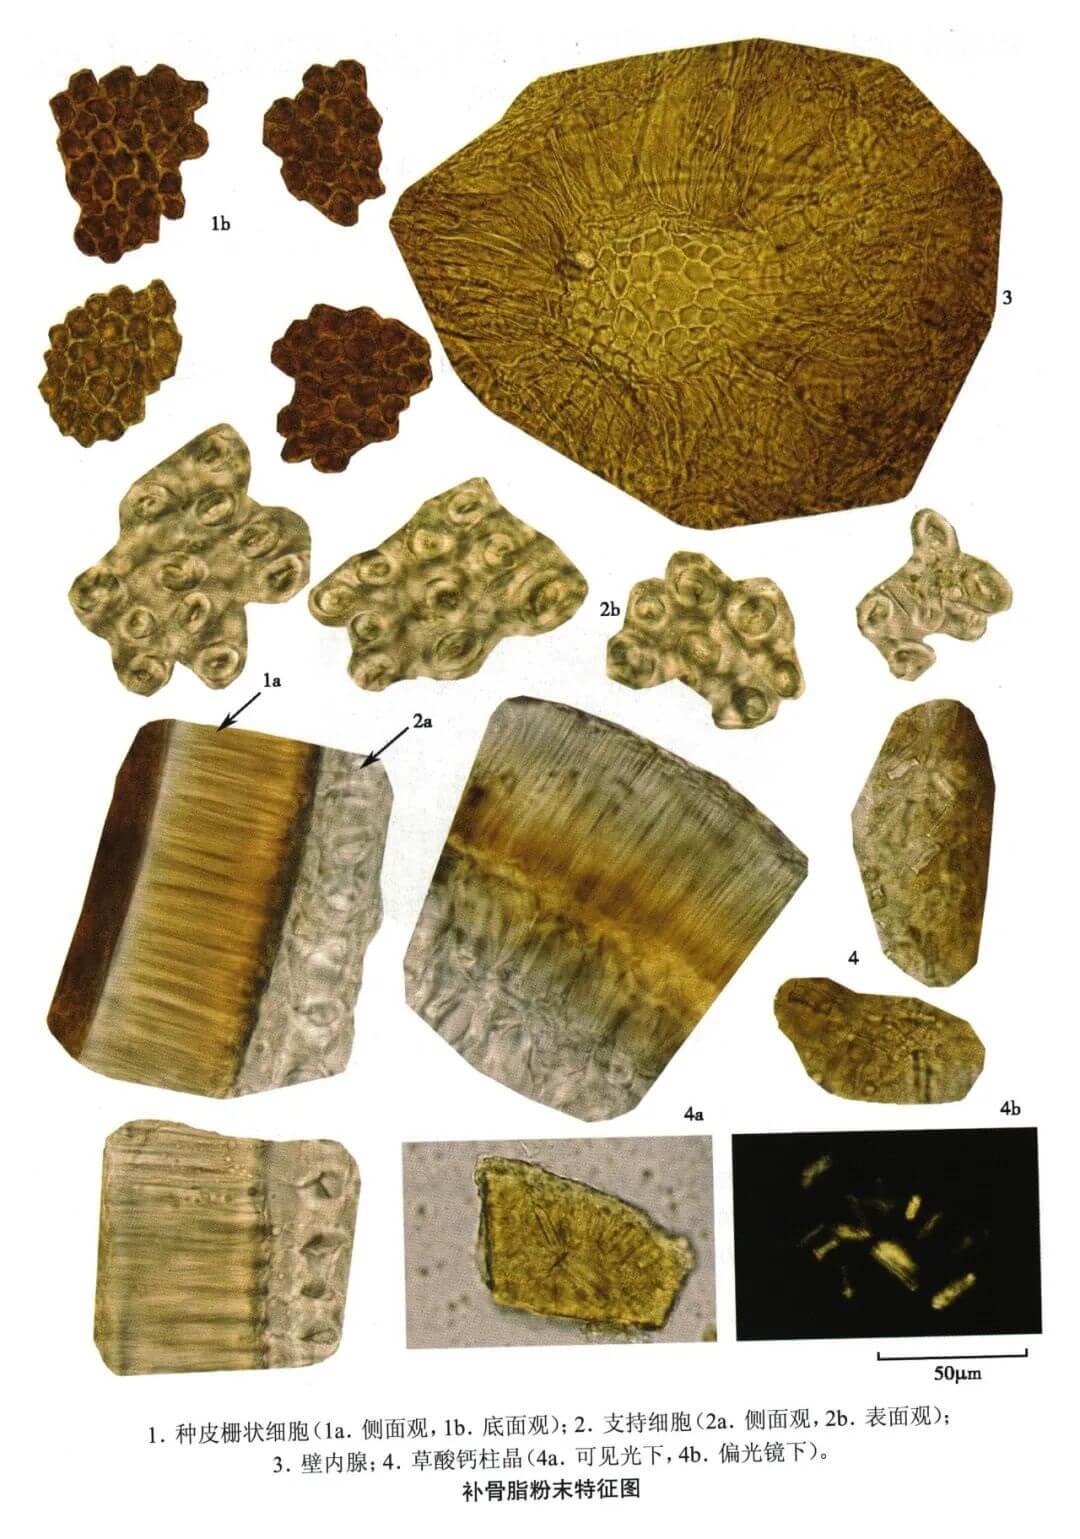

| 【显微鉴别】 本品粉末灰黄色。种皮栅状细胞侧面观有纵沟纹,光辉带1条,位于上侧近边缘处,顶面观多角形,胞腔极小,孔沟细,底面观呈圆多角形,胞腔含红棕色物。支持细胞侧面观哑铃形,表面观类圆形。壁内腺(内生腺体)多破碎,完整者类圆形,由十数个至数十个纵向延长呈放射状排列的细胞构成。草酸钙柱晶细小,成片存在于中果皮细胞中。 |

| 【显微重点】 种皮栅状细胞侧面观与底面观、支持细胞侧面观哑铃形,表面观类圆形。壁内腺多破碎,较难发现。 |

| 【图谱来源】 《中药成方制剂显微图典》 |